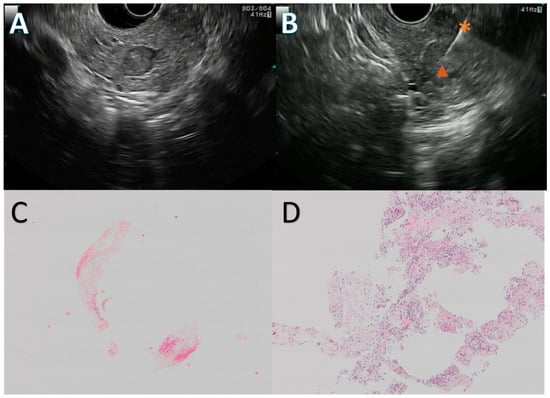

The EUS procedures were carried out in patients in left lateral position, under deep sedation, by three experienced endosonographists, using a linear array echoendoscope (GFUCT-140, 160 or 180, Olympus, Tokyo, Japan) and an FNB needle. The choice of the needle, between 20 G Procore, 22 G Procore (Cook Medical, Bloomington, IN, USA), or 22 G Acquire (Boston Scientific, Natick, MA, USA) was left to the discretion of the endosonographist. The stylet slow-pull technique was used in all instances, and two to three passes were performed, depending on the macroscopic on-site evaluation. The samples were collected and fixed in 10% formalin for 12–24 h, and then centrifuged. The specimen was embedded in paraffin, cut into 4 μm section, and stained with HES. A representative EUS FNB procedure and the corresponding histological slides are presented in Figure 2.

Figure 2. Endoscopic ultrasound guided fine needle biopsy (EUS FNB) of a pancreatic neuroendocrine tumor. Solid, 10 mm, hypoechogenic round lesion in the pancreatic head (A) first punctured with a 20 G Procore needle with inconclusive results, then with a 22 G Acquire needle (B) during a repeat EUS FNB. The first EUS FNB showed only fibrin and red blood cells (C), while the second one retrieved multiple neuroendocrine-like cells (D). Figure (C,D) are at ×4 magnification. The diagnosis was confirmed by a strong anti-synaptophysin antibody staining on immunohistochemistry. *: 22 G Acquire needle, : neuroendocrine tumor.